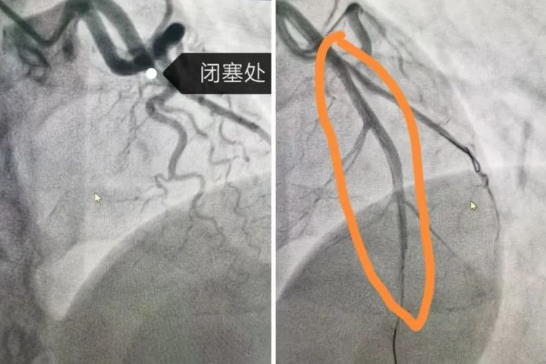

8點(diǎn)30分,導(dǎo)管室迎來了第一批患者,兩個(gè)手術(shù)間同時(shí)啟動(dòng)。第1手術(shù)間接診的是一位31歲的急性心肌梗死男性患者,他因胸痛和呼吸困難被緊急送醫(yī)。冠狀動(dòng)脈造影顯示,患者的左冠前降支完全閉塞,情況十分危急。在院長隋立有的帶領(lǐng)下,醫(yī)護(hù)團(tuán)隊(duì)緊密配合,迅速為患者實(shí)施了PCI手術(shù)。經(jīng)過緊張而有序的操作,成功開通了閉塞的血管,并植入一枚支架,恢復(fù)了血流,改善了心肌供血,挽救了這位年輕患者的生命。